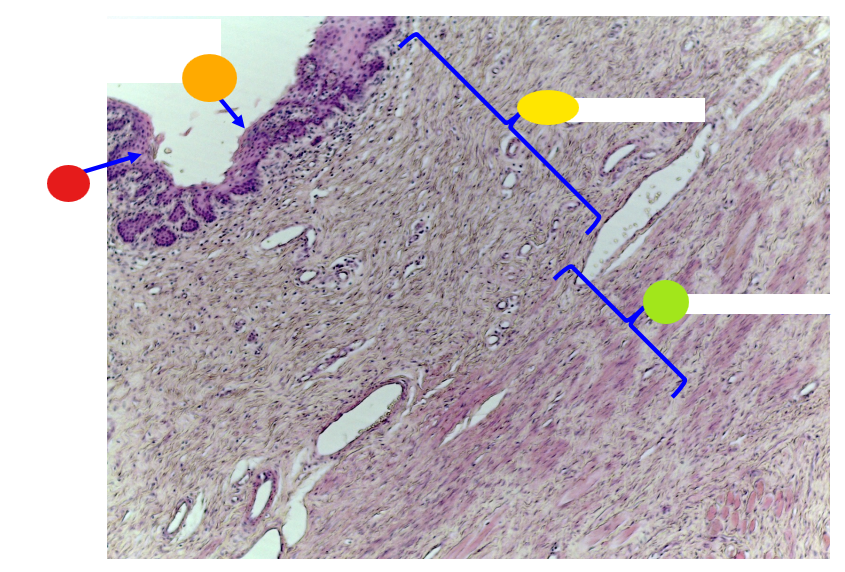

red

tunica albuginea

orange

primordial follicles

red

primary follicle

orange

secondary follicles

what is this

tertiary follicle